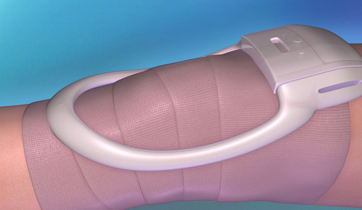

Pulsed Radio-Frequency Therapy

AMP Orthopedics,

Whitespace Healthcare Marketing

PRF Therapy is designed to accommodate the patient, the physcician, and the biotech marketer. It illustrates the MOA of a PRF device in treating inflammation. It also is compared to NSAIDs and other narcotics used for similar conditions.